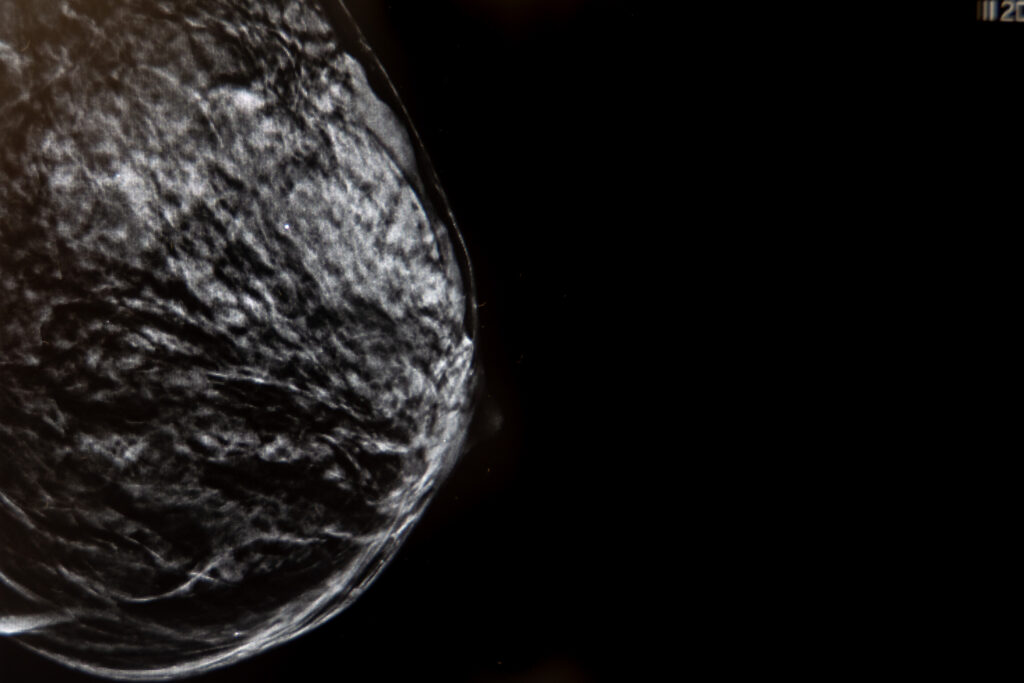

La mamografía con tomosíntesis, también conocida como mamografía 3D, es una técnica avanzada de imagen mamaria que utiliza rayos X de baja dosis para crear una imagen tridimensional de la mama. A diferencia de la mamografía tradicional, que proporciona una imagen bidimensional, la tomosíntesis captura múltiples imágenes desde diferentes ángulos, permitiendo una visualización más detallada del tejido mamario.

- Imágenes 3D: proporciona una visualización tridimensional de la mama, permitiendo una mejor detección de lesiones.

- Detección de lesiones ocultas: ayuda a detectar lesiones que podrían estar ocultas en una mamografía tradicional.